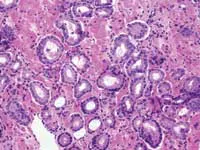

Gleason grading system; gene discovery

Zarbo: The issue of variation in pathologist interpretation of histologic biopsy secondary characteristics such as Gleason grade is well known. There exists the possibility of interobservor variation (e.g., between pathologists), as well as intraobservor (same pathologist) variation. Much of this variation can be diminished by standardization through education and training. For instance, the Johns Hopkins Pathology website provides a Gleason grading tutorial that may be helpful in illustrating images of critical grades, like grade 4, that may influence therapeutic decisions.

Tomaszewski: The Gleason grading system is the most powerful grading tool for the prediction of outcome amongst all the tumor systems. In almost every study ever performed, the Gleason grading system has statistically proven independent predictive value. Since, however, the Gleason grading system is a complex 10-level system, concordance levels in its application are only moderately good. The most critical threshold in the Gleason system is in the recognition of patterns 4 and 5. Once again, enhanced continuing medical education (CME) for pathologists is the most immediate remedy for improving the efficiency of patterns 4 and 5 recognition, and computer-assisted diagnosis (CAD) techniques could, in the future, facilitate this recognition. The public, however, must understand that even in the best of circumstances, the predictive power of the Gleason test is limited.

Tomaszewski: While many clinicians and most patients see the diagnosis of cancer as Yes, I have it or No, I do not have it, the reality of diagnostic certainty is not that simple. Currently, the diagnosis of prostate cancer can only be made by histopathological recognition. In essence, a diagnosis of prostate cancer is a probability statement based on morphology. The statement is that given a certain image pattern, there is a significant chance that the patient under examination will have disease progression, which will cause him morbidity or death. In 2004, this is first an issue of improving CME for pathologists. There are many false-positive and false-negative mimics. The role for more effective CME is to help pathologists assure their accuracy and effectiveness in diagnosis. Better training systems will help assure the reproducible separation of false positive from true positive and false negative from true negative. The case given in illustration highlights an apparent false-negative result.